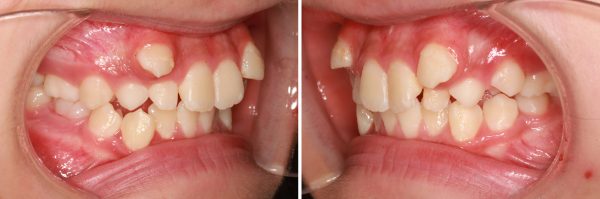

12歳 女性「”八重歯”を 治して欲しい」15か月(上下顎叢生)

12歳の 女性です。

お母さん、ご本人より「 ”八重歯” を治して欲しい」との事で来院されました。

よくある ”八重歯” の状態です。

左右ともに ”八重歯” の状態です。

正面から 2番目の歯が 裏に入り込んでいます。

また、上下の前歯が前に傾いているために、口もとが少し出ています

レントゲン写真を見ても 上下の歯が前に傾斜しています。

”八重歯” の影響と 歯が傾いているために口もとが 前に出ています。

意識しないと 口を閉じられません。口もとが ”もっさり”とした印象を受けます。

2番目の歯が裏に入っていますので、”八重歯”感が強くなっています。

何年も前から ”八重歯” が気になっていた との事で、大きな口を開けて笑いにくいそうです。

側切歯の口蓋側転位を伴う 上下顎叢生です。

「とにかく ”八重歯” を治してほしい」との事で、

上下左右の小臼歯抜歯を行い、抜歯空隙に歯を移動、排列しました。

2021年2月26日にスタートして、2022年5月26日に終了しました。

治療期間は15か月でした。

2番目の歯は歯列内へ きれいにならびました。 歯ならびもコンパクトになりました。

上下前歯の傾きが緩やかになり、

上下口唇状態が良好になりました。

上唇と下唇が 下がったことでバランスが整いすっきりとしました

口もとが出ていた感じも 修正され、口もとの ”ぼってり” とした雰囲気が改善しました。

”八重歯” はすっかり 解消し、